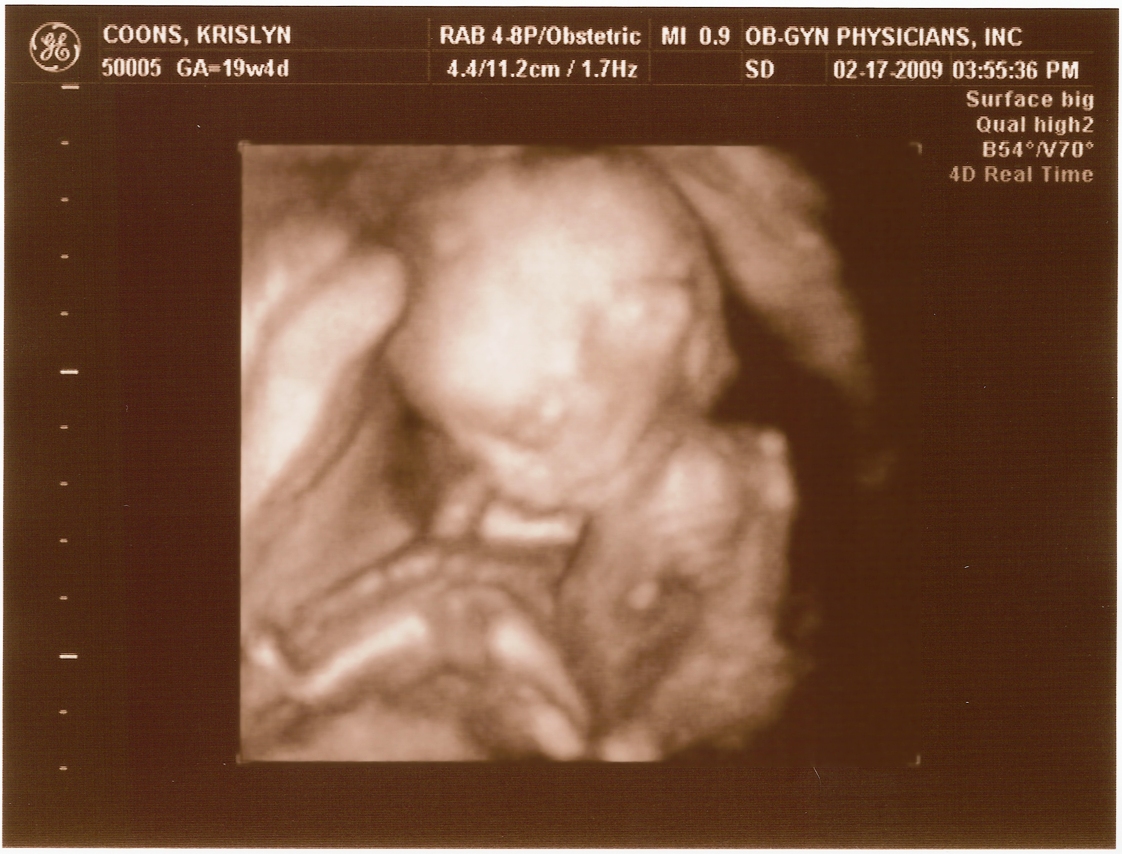

Ultrasound Pictures

20 weeks -

20 weeks